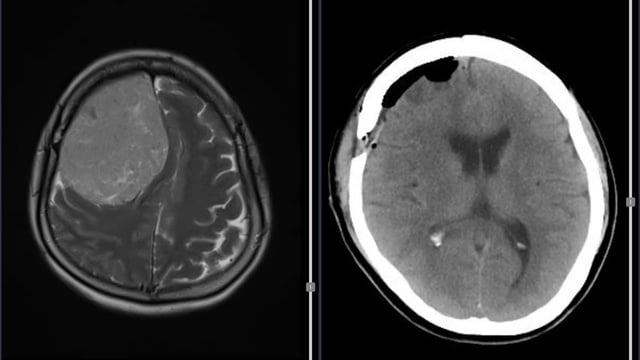

ຮູບພາບ MRI ຂອງຄົນເຈັບກ່ອນການຜ່າຕັດ (ຊ້າຍ), CT ຫຼັງຈາກການຜ່າຕັດ

ກ່ອນໜ້ານີ້, ຄົນເຈັບ K. ໄດ້ເຂົ້າໂຮງໝໍແລ້ວ ມີອາການປວດຫົວຮຸນແຮງ, ຮາກ ແລະ ອ່ອນເພຍຢູ່ບໍລິເວນຮ່າງກາຍເບື້ອງຊ້າຍ ເປັນເວລາປະມານ 6 ເດືອນ. ຮູບພາບ MRI ສະແດງໃຫ້ເຫັນວ່າເນື້ອງອກກໍາລັງກົດດັນຢ່າງຫນັກຕໍ່ໂຄງສ້າງຂອງສະຫມອງຂອງ hemisphere ຂວາ. ພາຍຫຼັງປຶກສາຫາລືກັບຜູ້ຊ່ຽວຊານແລະກະກຽມຢ່າງລະມັດລະວັງ, ວັນ ທີ 27 ຕຸລານີ້, ຄະນະກຳມະການຜ່າຕັດໄດ້ດຳເນີນການຜ່າຕັດເອົາເນື້ອງອກອອກທັງໝົດ. 4 ຊົ່ວໂມງຫຼັງຈາກການຜ່າຕັດ, ຄົນເຈັບຕື່ນຕົວ, ເຄື່ອນຍ້າຍແຂນຂາທັງສີ່ຢ່າງເປັນປົກກະຕິ, ຮູບພາບ CT scan ສະແດງໃຫ້ເຫັນວ່າເນື້ອງອກໄດ້ຖືກໂຍກຍ້າຍອອກຫມົດແລ້ວ. ຄົນເຈັບຫາຍດີ ແລະ ຫາຍດີພາຍຫຼັງການປິ່ນປົວ 5 ວັນ.